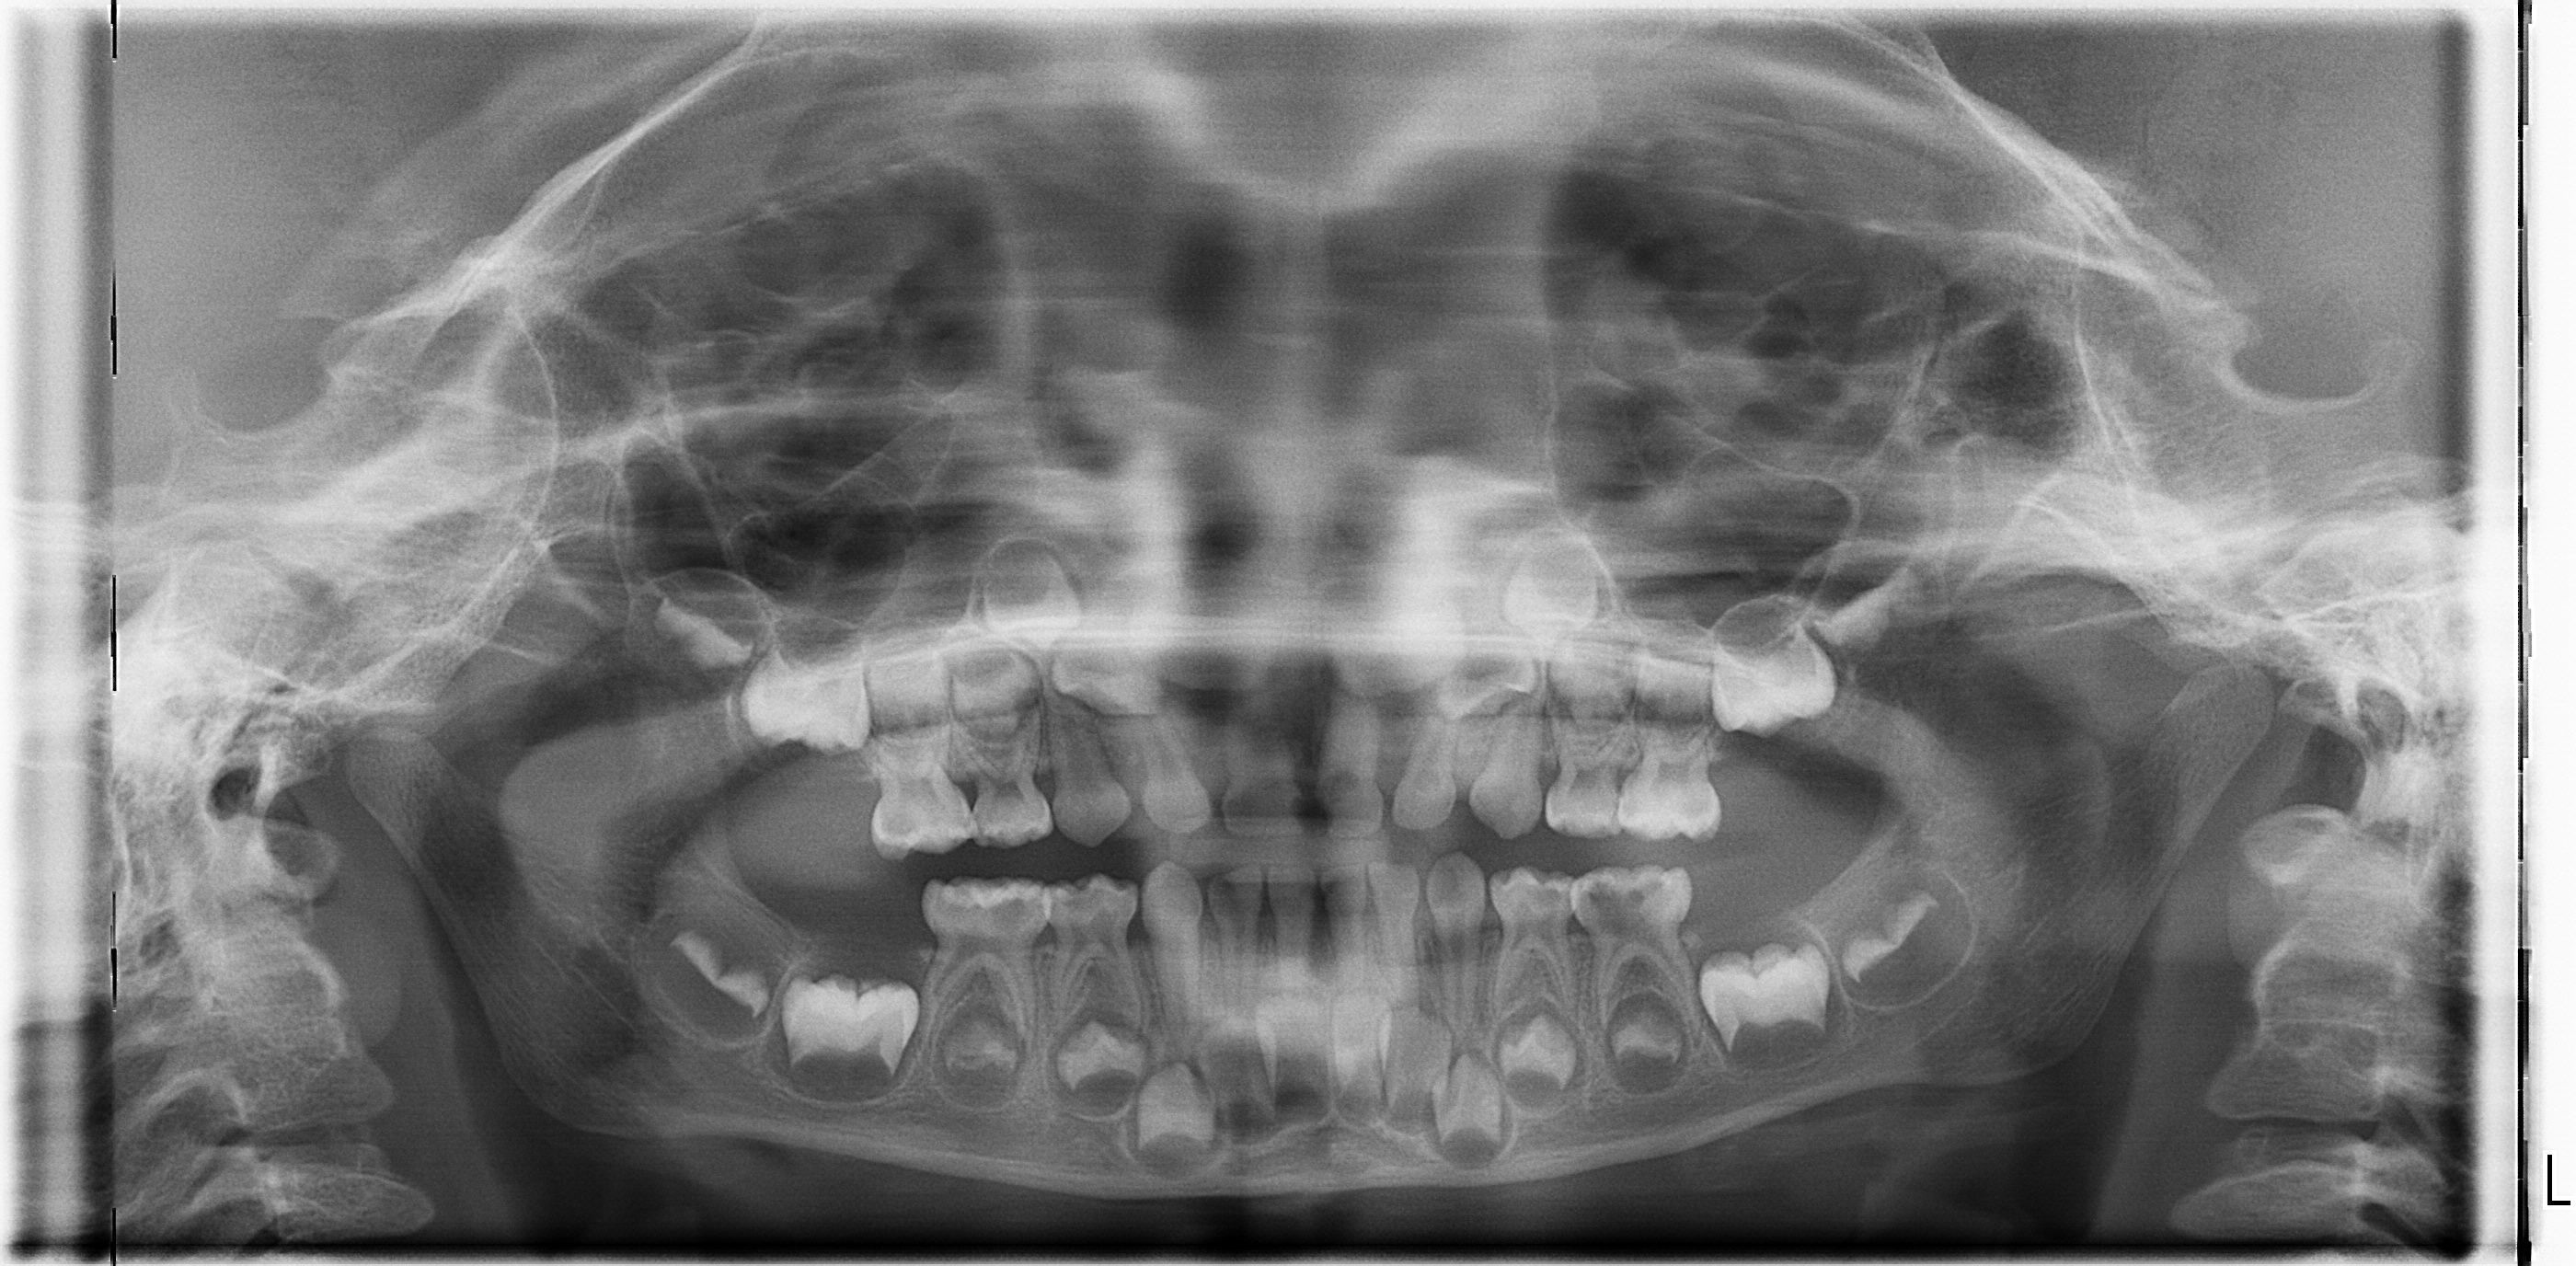

5岁小孩牙痛,有三颗牙烂了个洞 需不需要补牙? 给小孩拍的片,有颗牙发炎了,医生说要补牙治疗。 点击展开 匿名用户 2014-08-21 20:18 为您推荐: 其他回答 这个情况的话还是建议补上的,不然时间长的话这个会越来越严重的! 辉煌健康1978 2014-08-23 14:36 相关问题 我小孩4岁半有几颗牙虫蛀了,最近说牙痛需要补牙吗,能补吗? 快36周了,突然牙痛怎么办?可以去补牙吗? 关于孕晚期牙痛跟补牙的问题